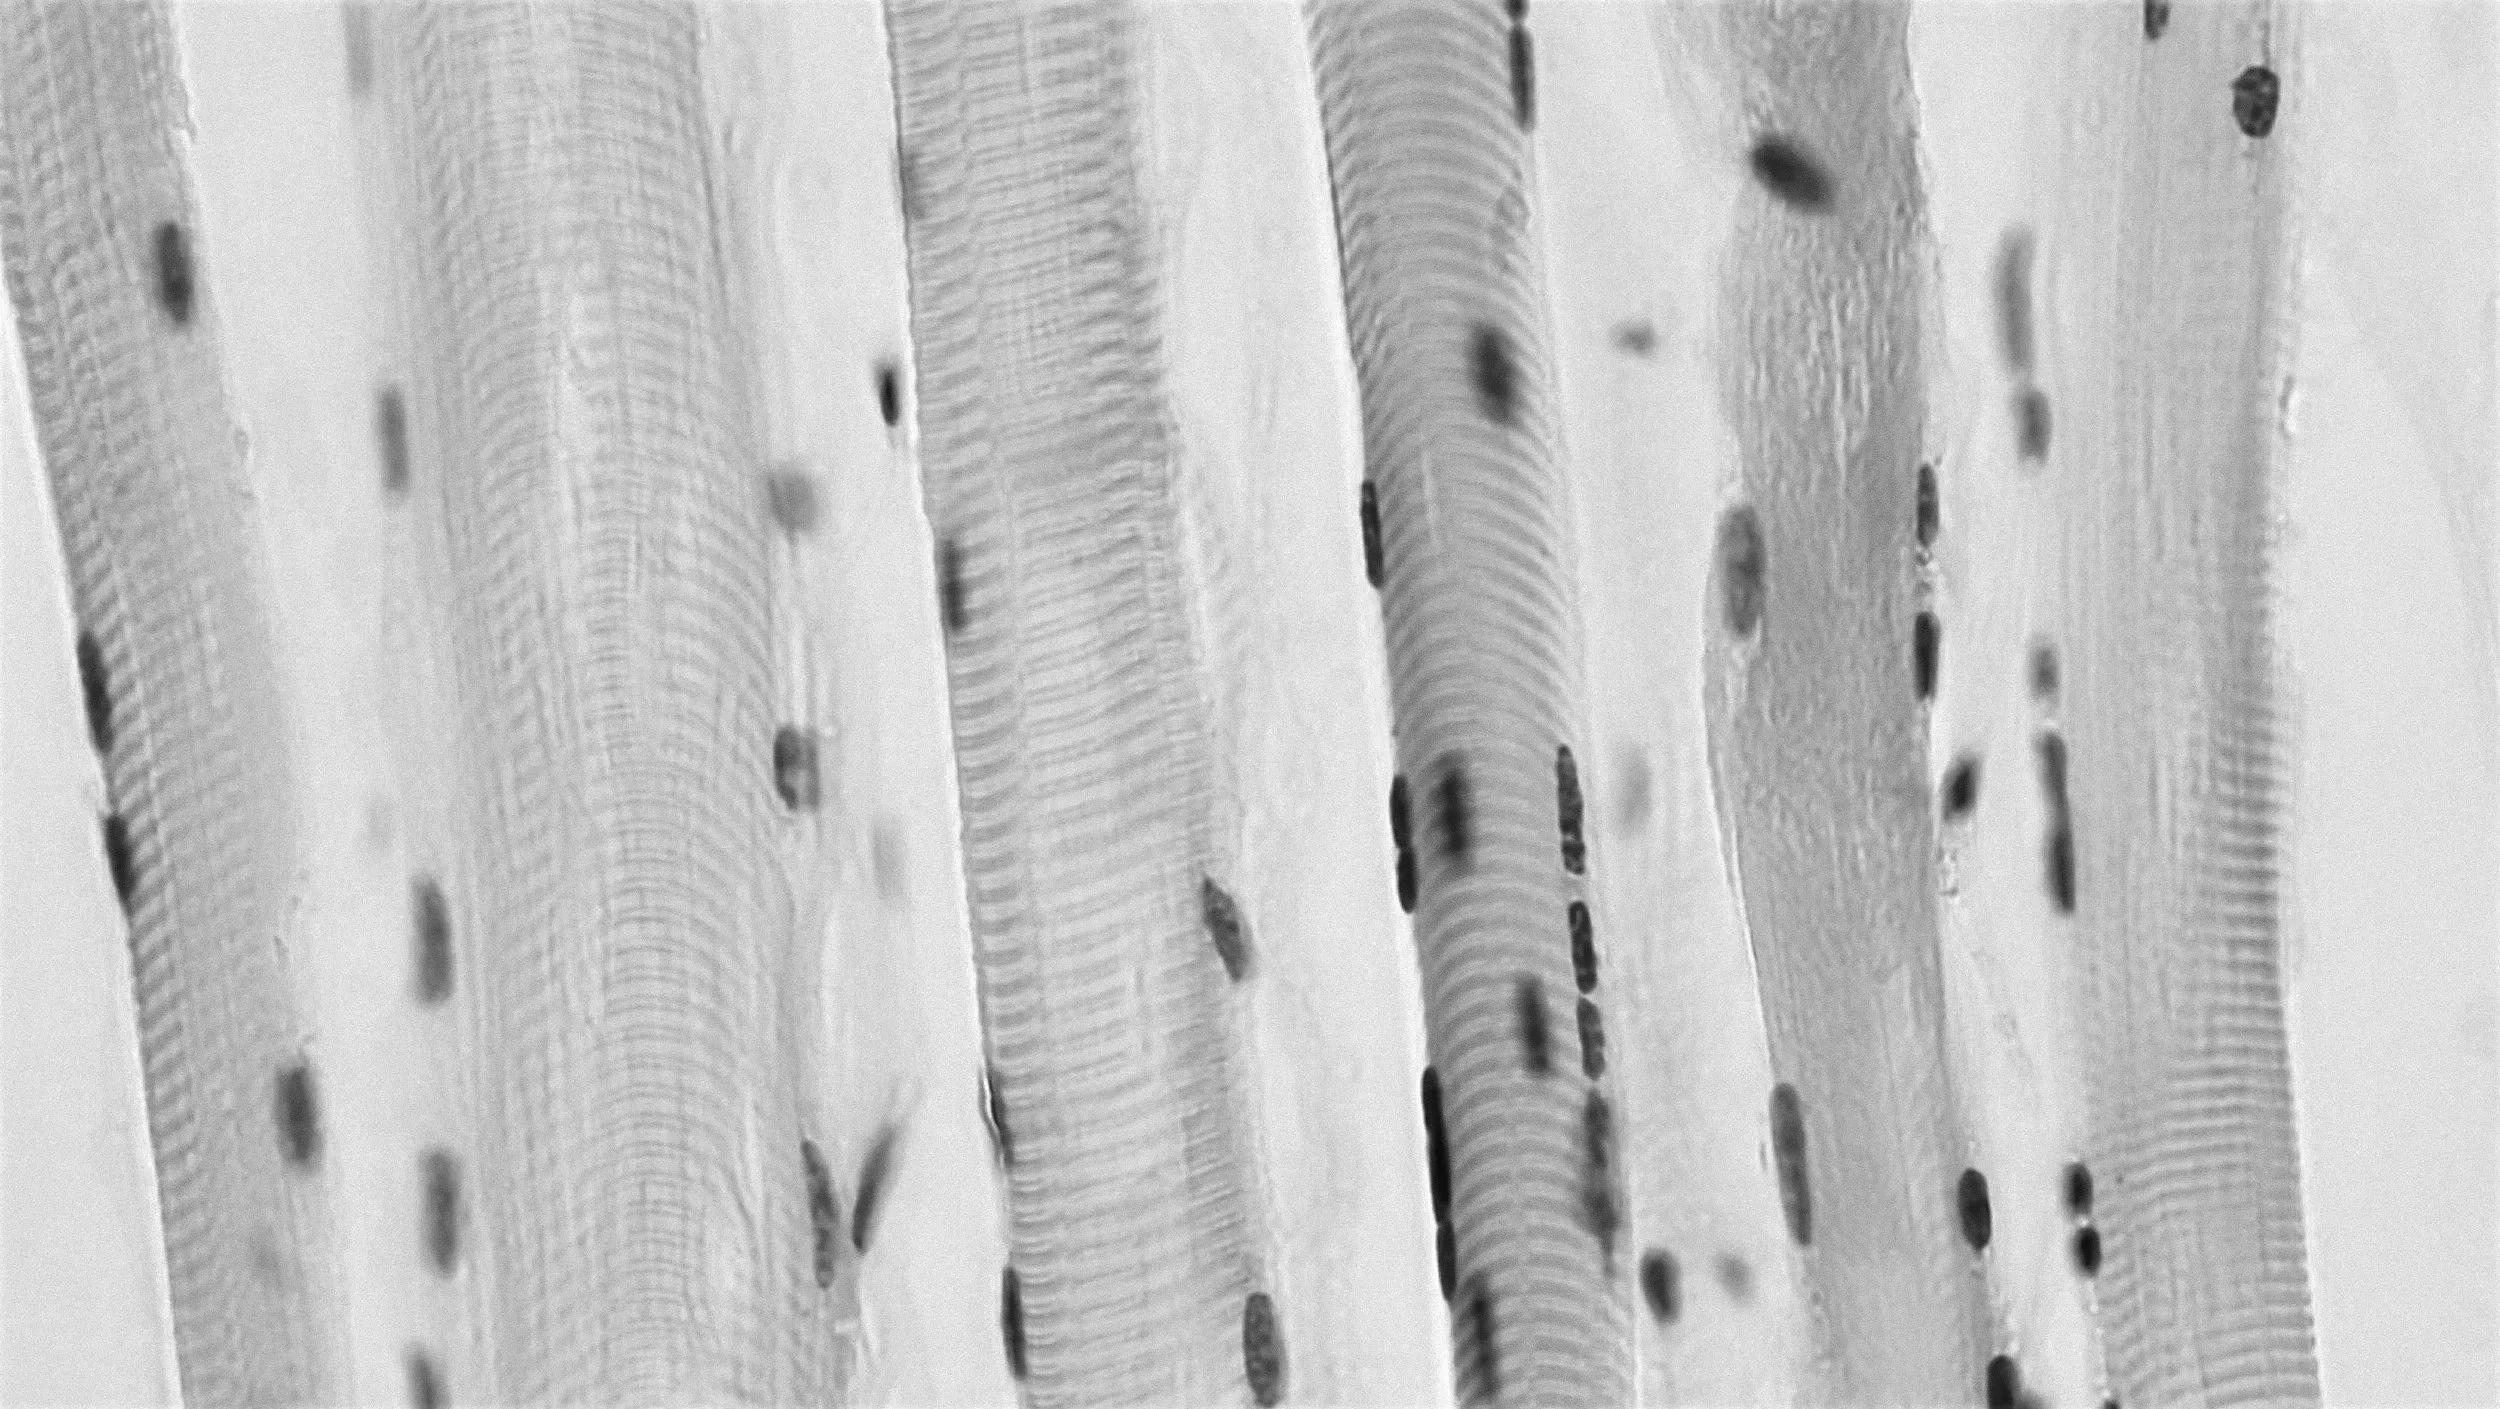

Gallery: DMM in development at the Sarcogenics lab

Remove cells, keep structure

Donor muscle tissue is processed to strip away all living cells, leaving behind the extracellular matrix — a natural scaffold made of proteins like collagen, laminin, and fibronectin.

Provide muscle-specific signals

This scaffold contains the physical alignment and chemical cues unique to skeletal muscle. These signals guide the body’s own stem cells and support blood vessel and nerve ingrowth essential for real muscle regeneration.

Skeletal muscle is unique: Aligned fibers, satellite stem cells, and neuromuscular junctions allow for extraordinary regeneration. But in severe injuries, the muscle's capacity to regenerate is lost. The components of Sarcogenics’ Decullarized Muscle Matrix began in an academic laboratory and include:

Decellularized scaffold: A whole-muscle derived extracellular matrix stripped of immunogenic cells while preserving pro-regenerative architecture.